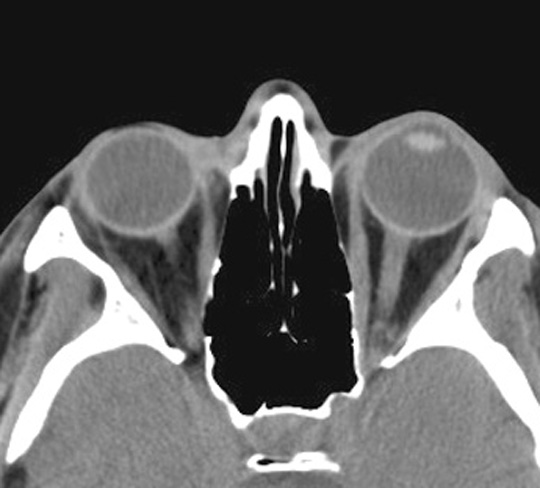

Identify the medial and lateral recti. Click the image for labeling.